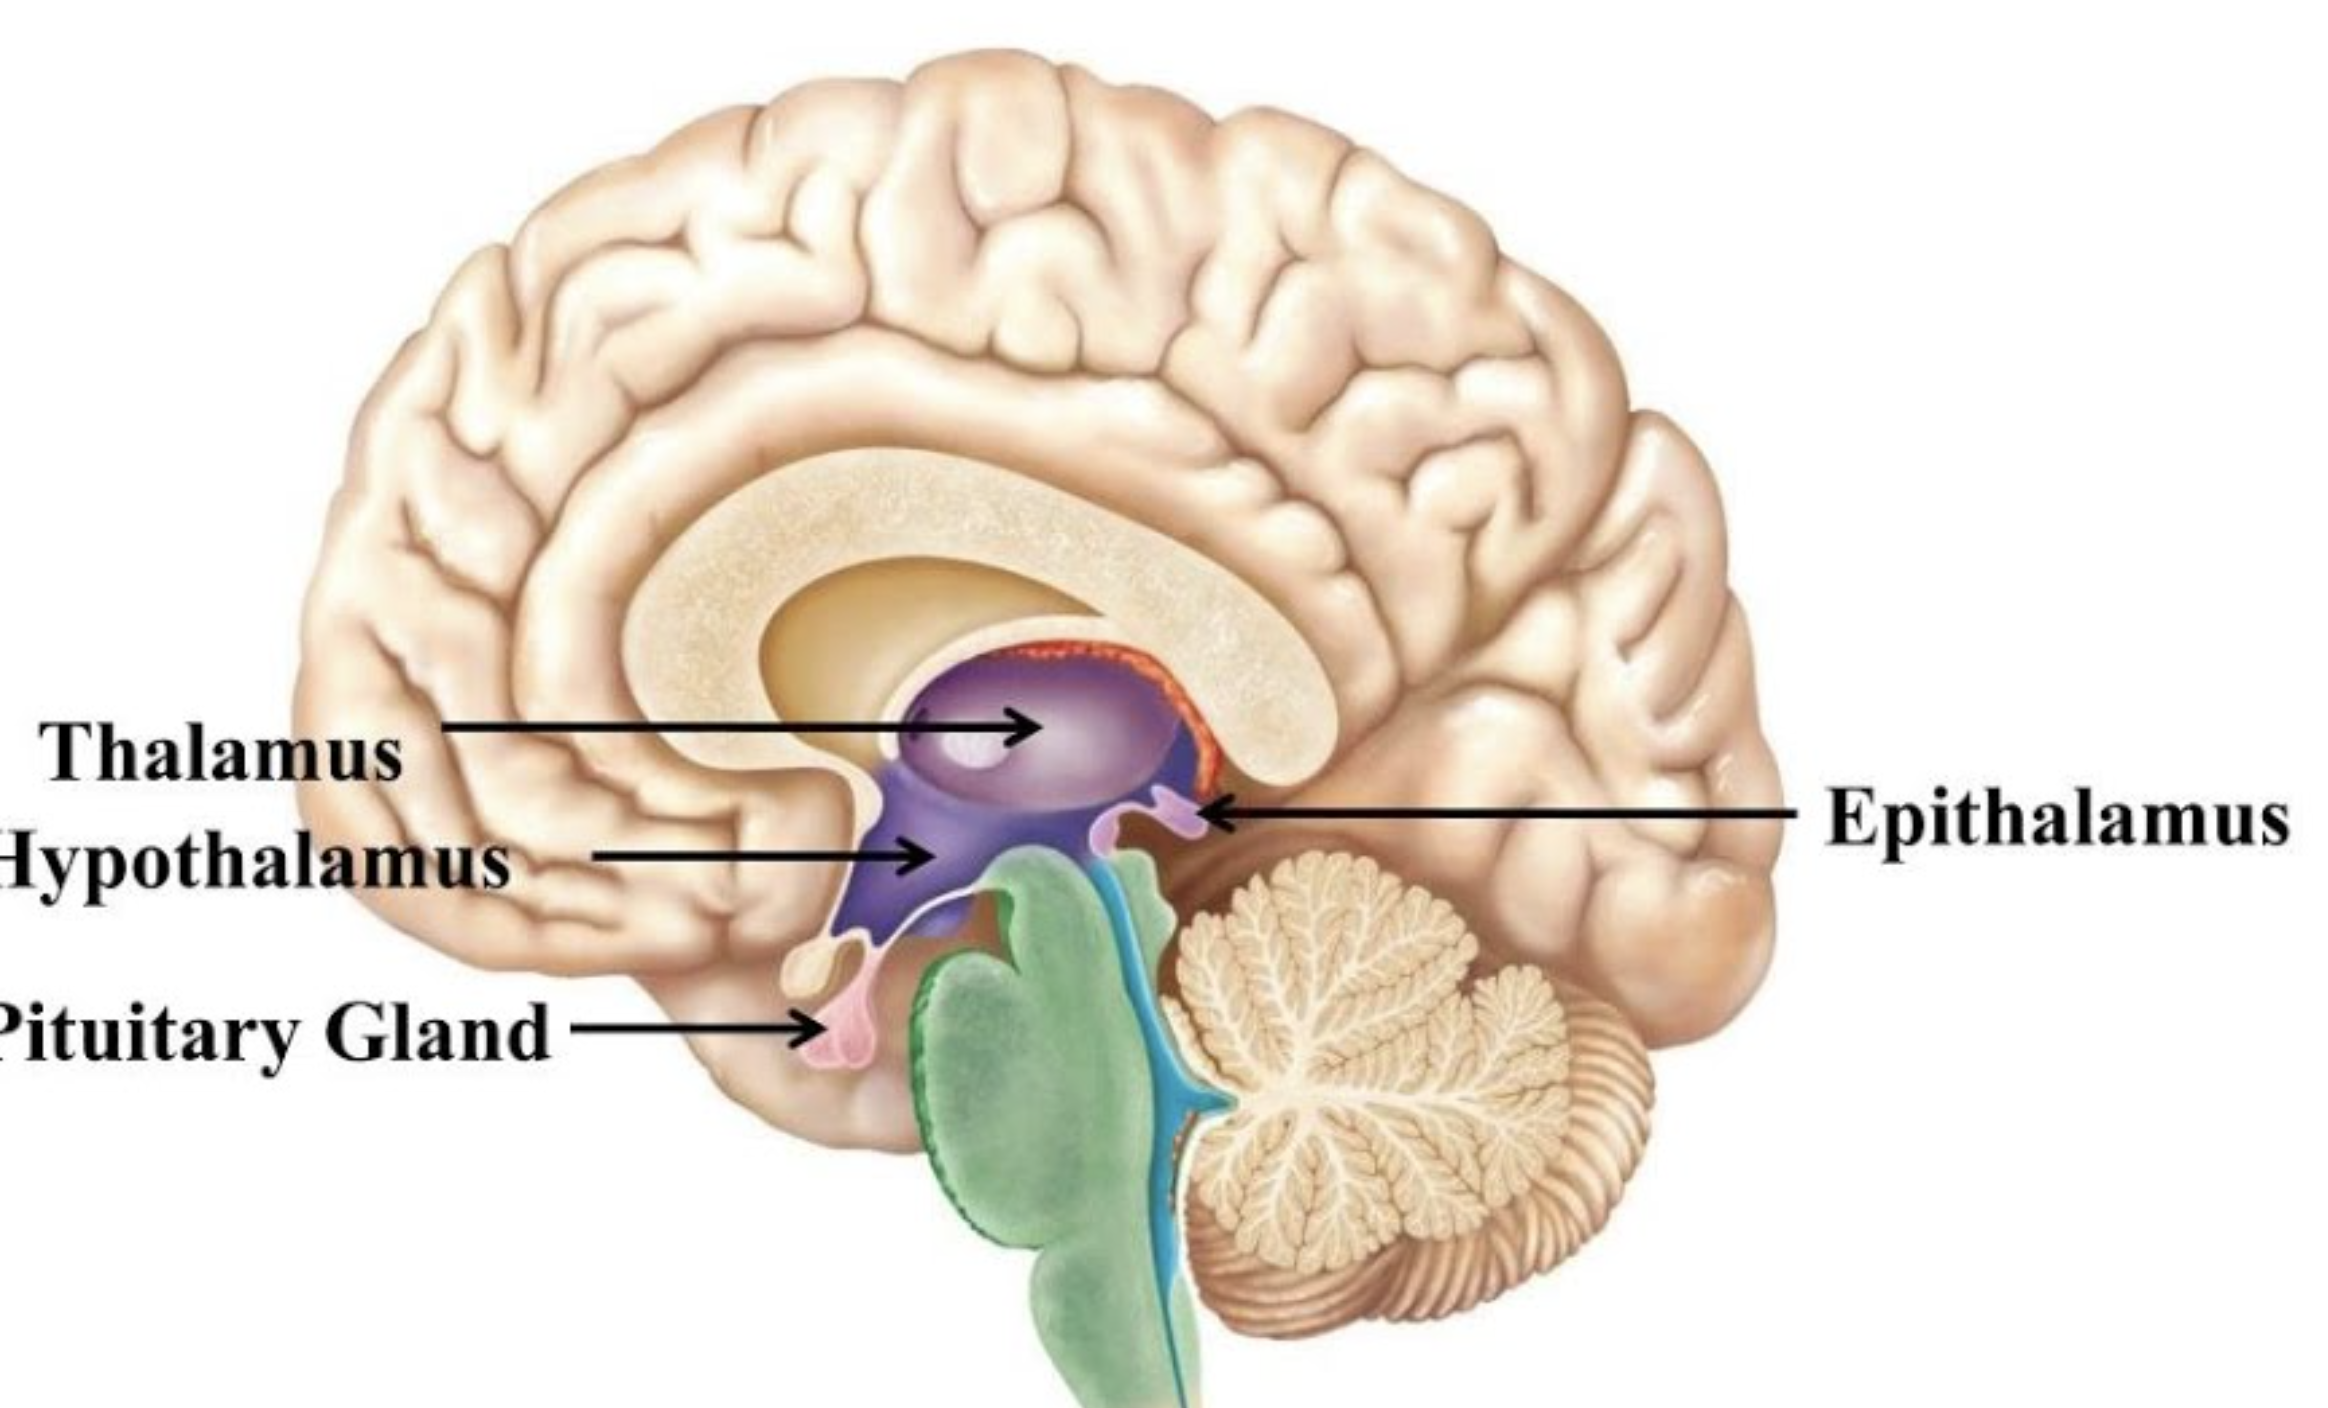

Which brain region is responsible for homeostatic control (hormonal, temperature regulation)?

Diencephalon

Which Diencephalon structure contains the Pineal Gland(secretes Melatonin)

Epithalamus

Which structure is a switchboard where neurons synapse to get to the precentral gyrus?

Thalamus

Which structure is the master control of the ANS and endocrine system, and regulates body temp/sleep/intake?

Hypothalamus

This region of the diencephalon helps to regulate the human circadian cycle (24-hour cycle).

It’s the Pineal Gland